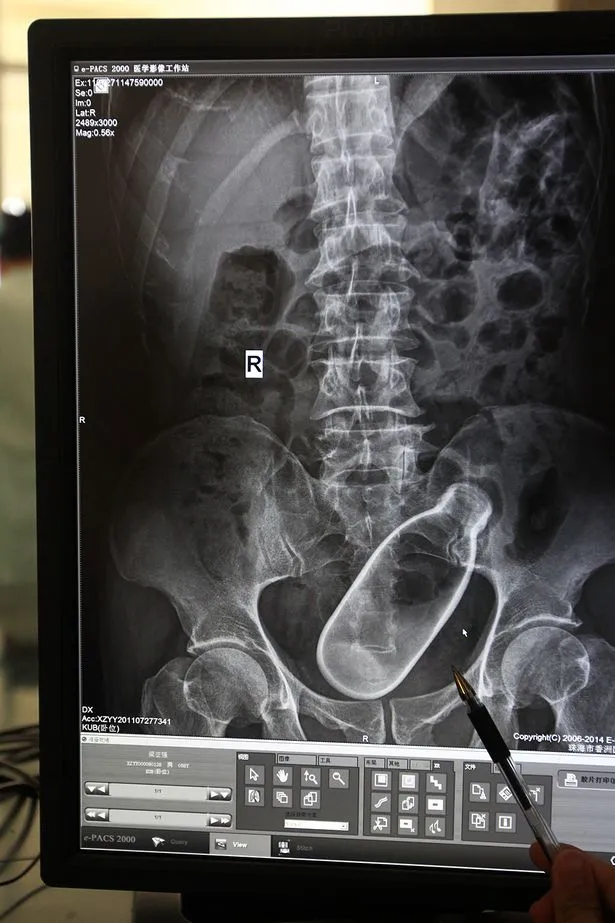

Ảnh chụp X-quang bụng chậu của một người đàn ông 60 tuổi đến từ Chu Hải, tỉnh Quảng Đông (Trung Quốc), cho thấy một chai nước đã được nhét vào bên trong hậu môn của ông.

Chai nước trong hậu môn của một người đàn ông Trung Quốc. (Ảnh: Mirror)